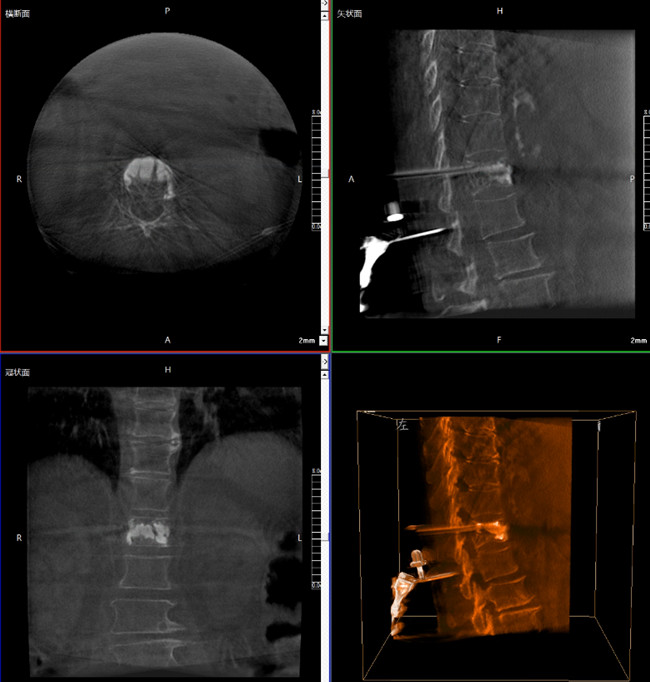

步驟一:C形臂三維重建+機(jī)器人手術(shù)規(guī)劃

使用普愛醫(yī)療三維C形臂對(duì)患者進(jìn)行胸椎影像掃描及三維重建,圖像被同步傳輸?shù)狡諓坩t(yī)療骨科機(jī)器人導(dǎo)航系統(tǒng)。

借助骨科機(jī)器人的規(guī)劃軟件進(jìn)行術(shù)前手術(shù)路徑模擬規(guī)劃,找到穿刺位置和角度,操作機(jī)械臂快速完成手術(shù)入點(diǎn)的準(zhǔn)確定位。

*術(shù)前規(guī)劃